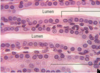

This type of epithelial cell is actually attached to the basement membrane even though it sometimes doesn’t appear to be that way Where two places are they commonly found?

Simple Pseudostratified Upper Respiratory Tract and trachea

Look at diagram for pseudostratified epithelium and know goblet cells, basal cells, epithelial cells, basement membrane, lamina propria, terminal bars, mucua, cilia, etc